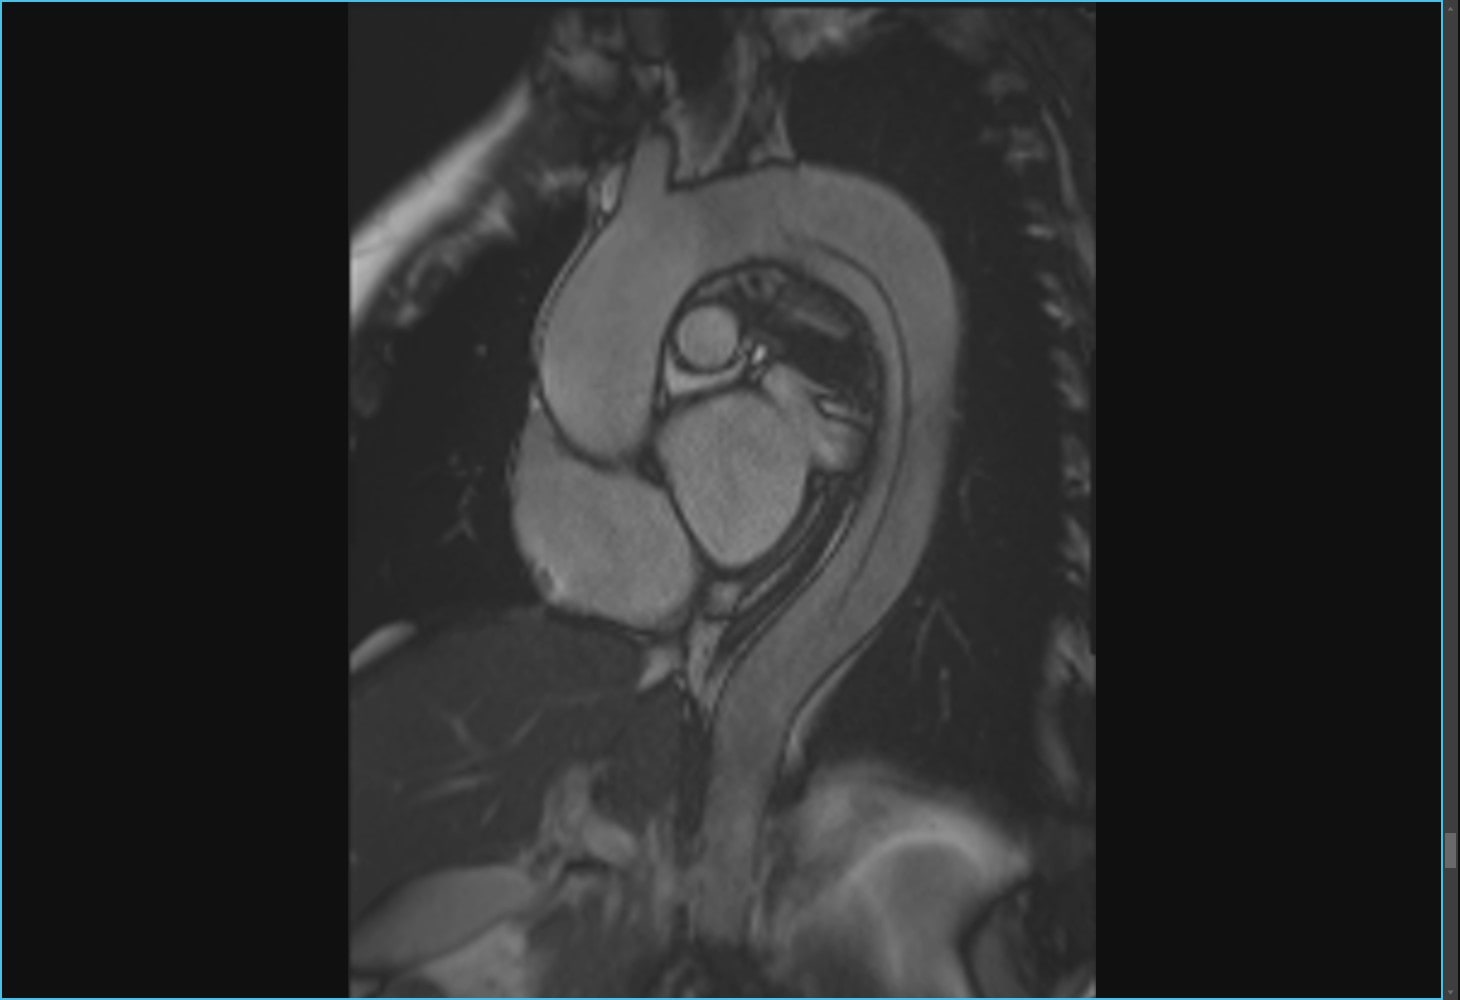

閉塞性肥大型心筋症の心臓に経皮的中隔心筋焼灼術 (PTSMA)を施した画像ですが、MRIでは造影剤を用いる事なく心臓の動きを捉えることができるだけでなく、エタノールにより壊死させた中隔心筋を明瞭に描画することができるので治療効果の判定に有用です。

PTSMA前

PTSMA後